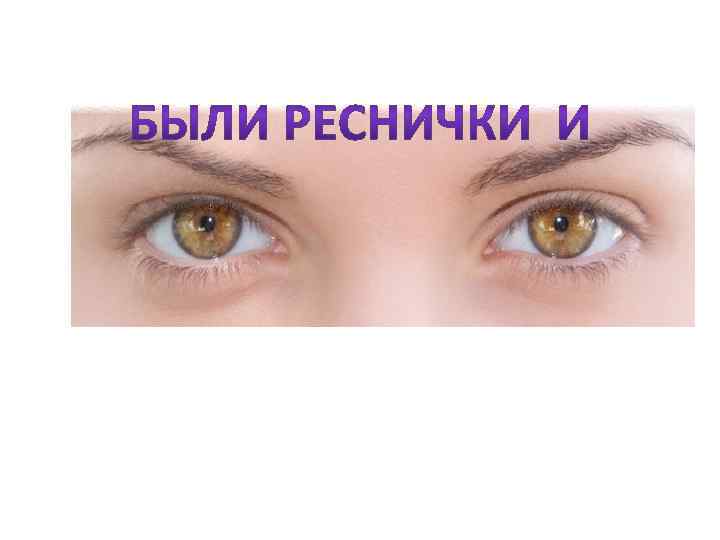

Факторы риска Недостаточное увлажнение дыхательной смеси Высушивание трахеи и бронхов

Факторы риска Недостаточное увлажнение дыхательной смеси Высушивание трахеи и бронхов

Факторы риска Недостаточное увлажнение дыхательной смеси ! Слизистая оболочка трахеи и бронхов обязательно должна быть укрыта секретом

Факторы риска Недостаточное увлажнение дыхательной смеси ! Слизистая оболочка трахеи и бронхов обязательно должна быть укрыта секретом

Факторы риска Недостаточное увлажнение дыхательной смеси • естественное удаление бактерий • состояние эпителия трахеи и бронхов

Факторы риска Недостаточное увлажнение дыхательной смеси • естественное удаление бактерий • состояние эпителия трахеи и бронхов

Движение клеток реснитчатого эпителия Движение вперед 1 – 3 Обратное движение 4 – 8

Движение клеток реснитчатого эпителия Движение вперед 1 – 3 Обратное движение 4 – 8

Оптимальное увлажнение Достаточная продукция слизи Хороший транспорт Экономит энергию и воду Защитная функция

Оптимальное увлажнение Достаточная продукция слизи Хороший транспорт Экономит энергию и воду Защитная функция